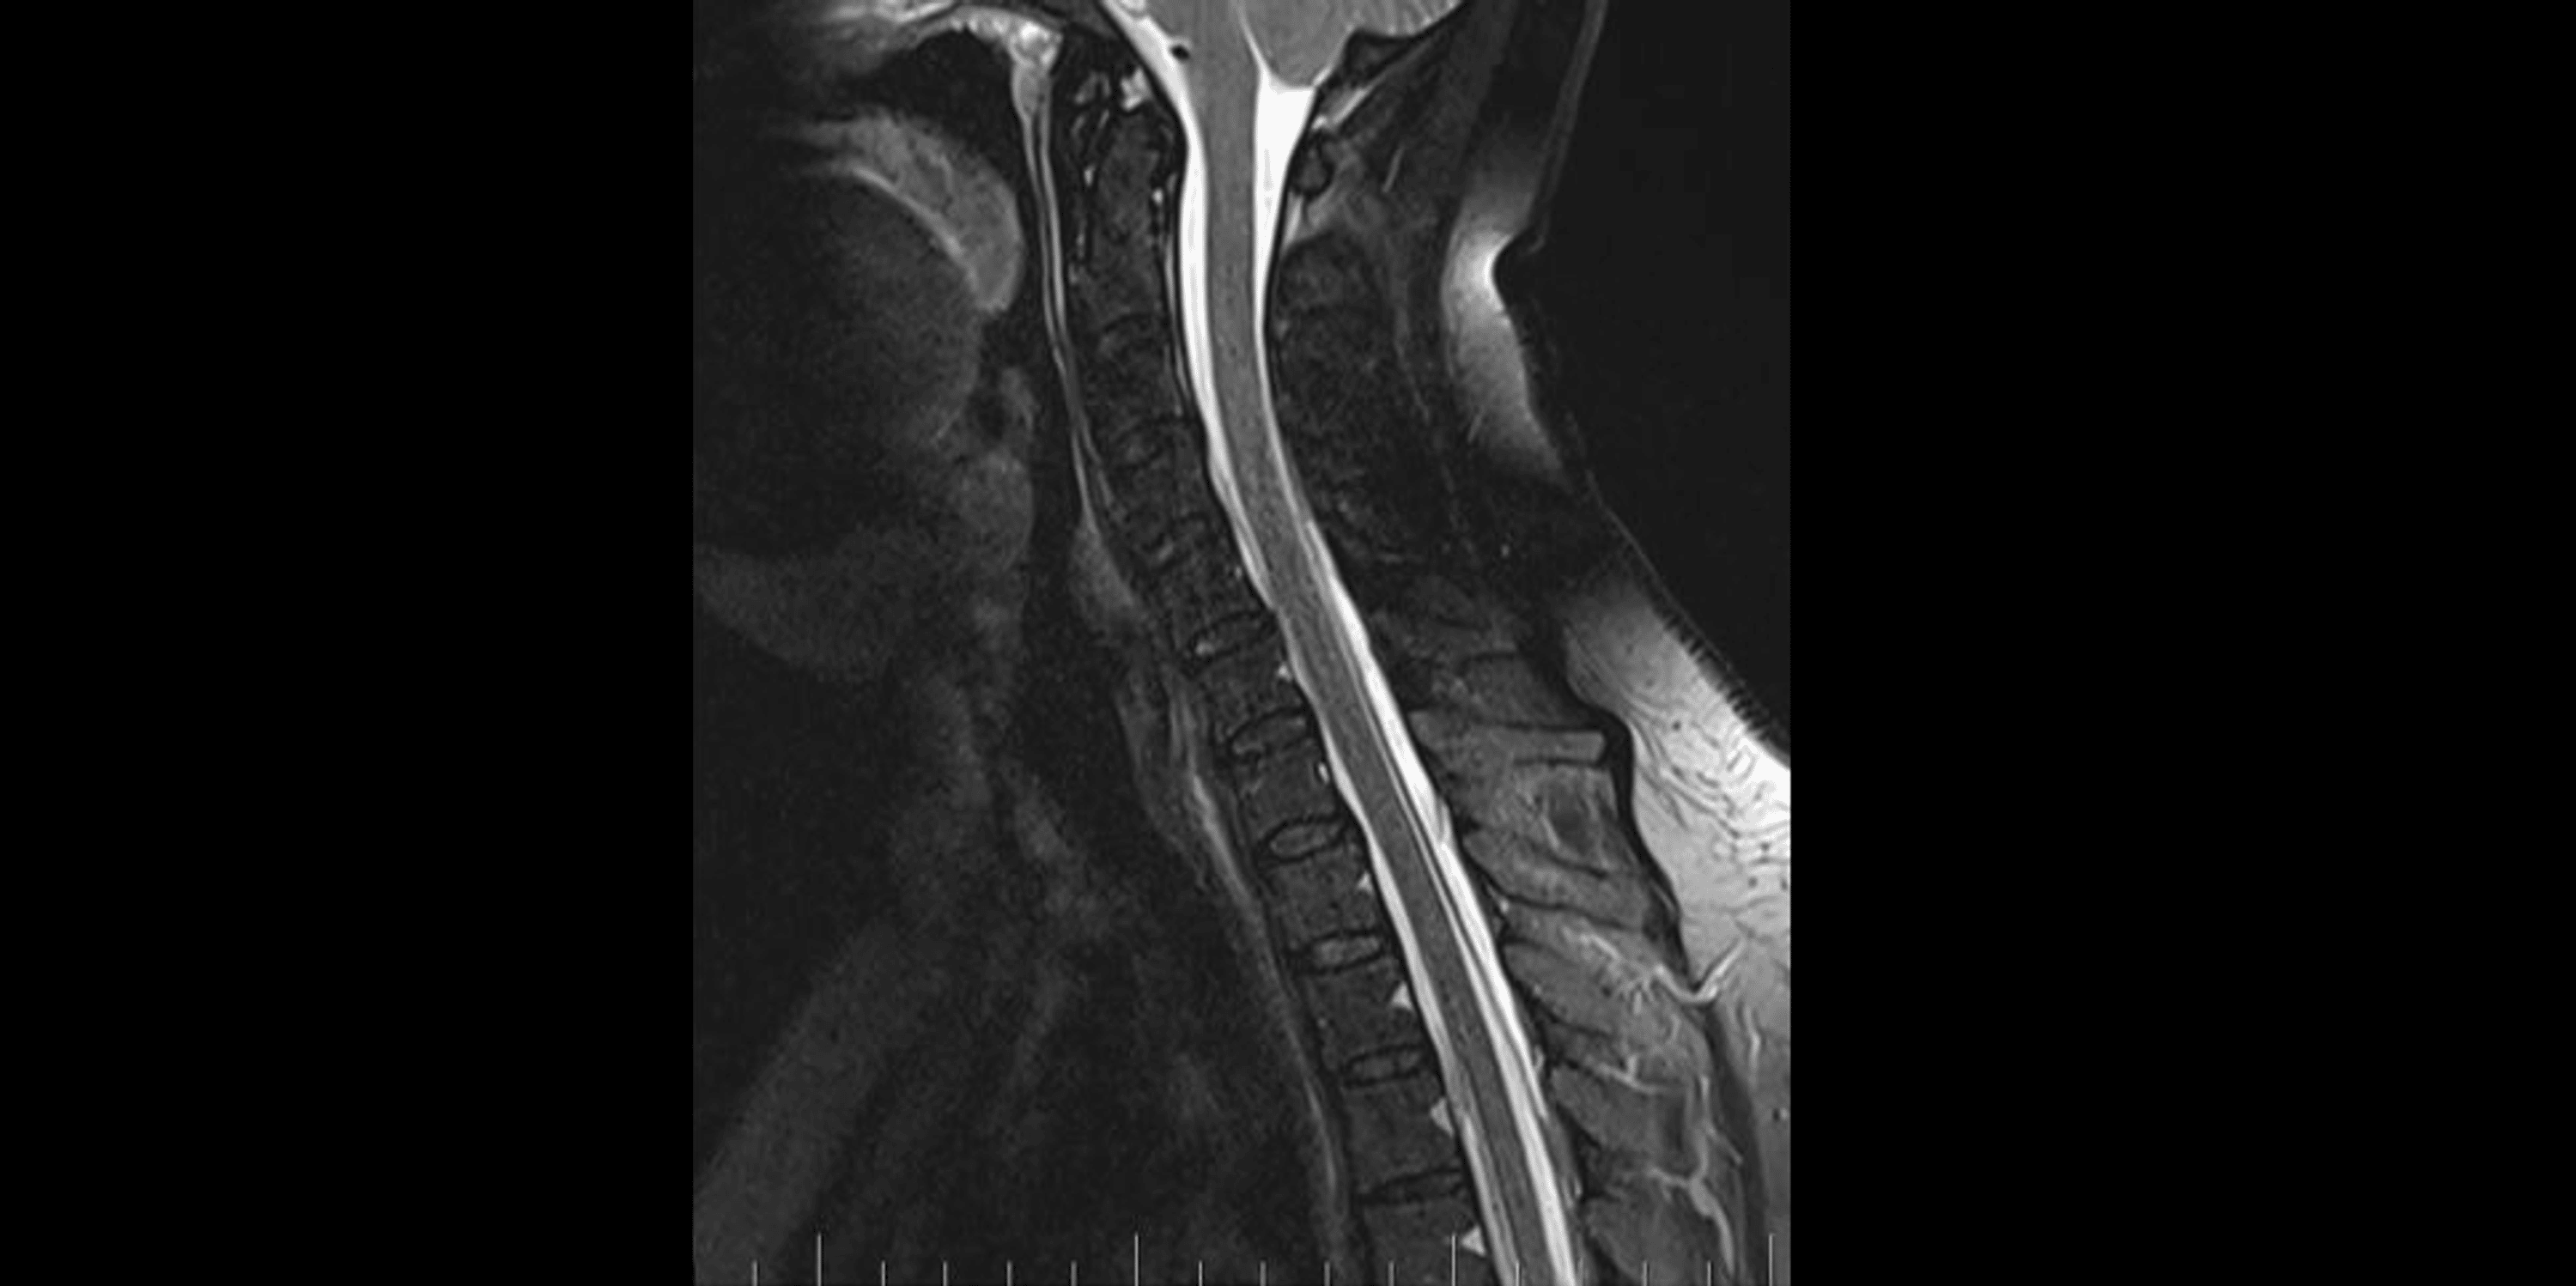

A brain and C spine MRI scan on March 5, 2023 (one month after the procedure) showed a regression of the subdural collection from 5.00 mm to 2.5 mm in the parietal area but all other parameters remained unchanged (Figure 3).

MRI myelography (Figure 4) showed no CSF leak. The SLEC was almost totally absorbed and only a tiny residuum persisted. The patient reported significant headache relief.